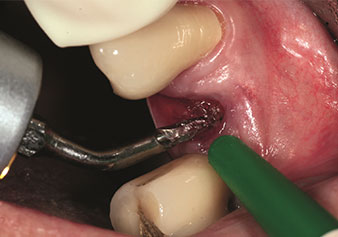

Internal sinus lift

W&H also offers the perfect solution for the internal sinus lift.

Following preparation of the maxillary sinuses with the corresponding instrument set (Fig. 3), the new Z35P instrument (Fig. 4) is used to lift the membrane hydrodynamically. The same instrument set can also be used for piezosurgical preparation of the implant bed in increasing diameters (Figures 3 and 4 included with the kind permission of Dr Mario Kirste, Frankfurt/Oder).

Preparation of maxillary sinus floor and lifting of Schneiderian membrane (Z35P instrument)

Fig. 4: Preparation of maxillary sinus floor and lifting of Schneiderian membrane (Z35P instrument). Photo: © Dr Mario Kirste (Frankfurt / Oder)